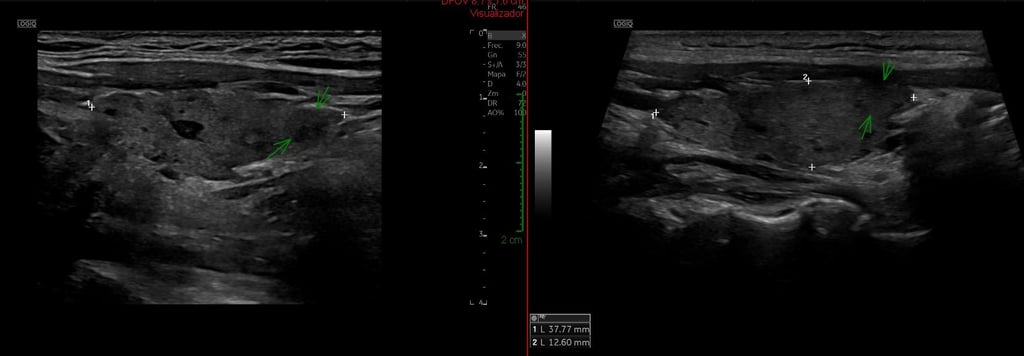

Diciembre 2024

Octubre 2025

Rosa acudió a nosotros con un hipotiroidismo de Hashimoto y pérdida de la energía. En menos de un año, su glándula tiroides ha perdido los quistes coloides y mejorado los nódulos sólidos. Clínicamente, su mejoría ha sido completa, con retorno a algunas de las actividades que no podía ejercer, y a un estilo de vida inimaginable en tan breve plazo de tiempo.

Todo con una reducción dramática de las hormonas exógenas, y en proceso de retirada de toda la medicación.